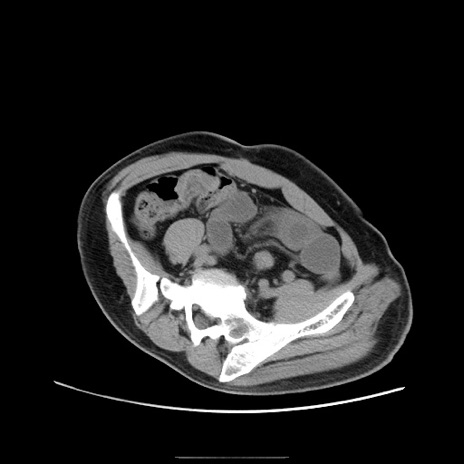

症例22(横断像)

【症例】50歳代男性

【主訴】腹痛

【現病歴】AVMからの被殻出血のため回復期リハ病棟入院中。 本日午後3時頃急に下腹部痛が出現した。

【既往歴】AVM、被殻出血、虫垂炎、高血圧

【身体所見】意識晴明、左半身不全麻痺、会話の理解は良好、36.5°C、腹部:膨隆、全体に板状硬、下腹部正中に圧痛点あり、反跳痛-、筋性防御不明、右下腹部にope scar

【データ】WBC 9400、CRP 0.06